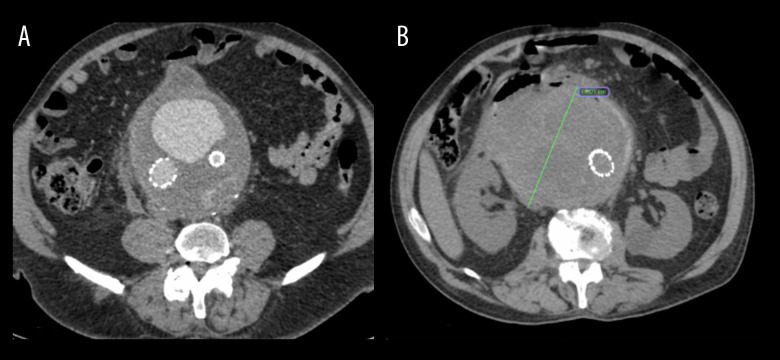

主动脉-十二指肠瘘(ADF)是主动脉和十二指肠之间的交通,需要紧急主动脉修复。然而,它经常导致危及生命的并发症。因此,早期和适当的诊断方法是必要的,以提供充分的治疗。本报告描述了一名68岁男性患者,在使用口腔造影计算机断层扫描(CT)对14厘米腹主动脉瘤(AAA)进行紧急血管内修复后出现肛肠-十二指肠瘘的病例,并讨论了延迟治疗和ADF管理的后果。我们报告一例68岁白人男性腹部腹胀,经进一步检查诊断为AAA,并通过血管内动脉瘤修复(EVAR)成功治疗。然而,1年后,发现了一个漏洞,尽管医生的努力,但由于患者连续数年推迟治疗,整体治疗变得复杂。动脉瘤继续扩大,直到达到14厘米。尽管血管内瘘成功修复,但通过CT和口腔造影诊断为十二指肠主动脉瘘(DAF)。患者保守处理动脉瘤囊引流和抗生素治疗,减少了动脉瘤囊的大小。尽管进行了早期诊断和干预,但由于进一步的并发症,患者的病情恶化,最终导致死亡。结论:本病例报告表明,在其他方法无法检测DAF的情况下,CT联合口腔造影在检测DAF方面具有潜在的有用诊断作用,并强调了及时干预以预防危及生命的并发症的重要性。然而,需要进一步的研究来探索潜在的机制及其可复制性。

BACKGROUND Aorto-duodenal fistula (ADF) is a communication between the aorta and the duodenum and requires urgent aortic repair. However, it often leads to life-threatening complications. Thus, an early and appropriate diagnostic method is necessary to deliver adequate treatment. This report describes the case of a 68-year-old man with anaorto-duodenal fistula following emergency endovascular repair of a 14-cm abdominal aortic aneurysm (AAA) identified using oral contrast computed tomography (CT), and discusses the consequences of delayed treatment and ADF management. CASE REPORT We present a case of a 68-year-old White man with abdominal bloating, who upon further examination was diagnosed with an AAA, which was successfully treated by endovascular aneurysm repair (EVAR). However, 1 year later, an endoleak was discovered and, despite the physicians' efforts, the overall treatment was complicated due to the patient's continuous postponement of treatment over several years. The aneurysm continued to expand until it reached 14 cm. Despite the successful endovascular repair of the endoleak, a duodeno-aortic fistula (DAF) was diagnosed using CT with oral contrast. The patient was managed conservatively with aneurysmal sac drainage and antibiotic therapy, which decreased the size of the aneurysmal sac. Despite early diagnostic efforts and interventions, the patient's condition deteriorated due to further complications, ultimately resulting in death. CONCLUSIONS This case report demonstrates a potential useful diagnostic role of CT with oral contrast in detecting DAF, in situations when other methods fail to do so, and emphasizes the importance of prompt intervention to prevent life-threatening complications. However, further investigations to explore the underlying mechanism and its replicability are required.